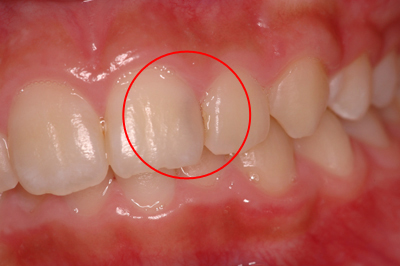

虫歯治療例

虫歯

虫歯を詰めた後